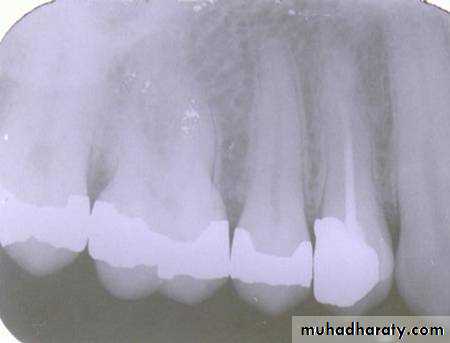

TEST

Is the composite restoration on tooth # 8 (arrows) located on the buccal or lingual?

canine filmincisor film

1

The restoration is located on the buccal. The tube head moves mesially from the canine film to the incisor film (x-ray beam projected more distally) and the composite moves distally, which is the opposite direction.